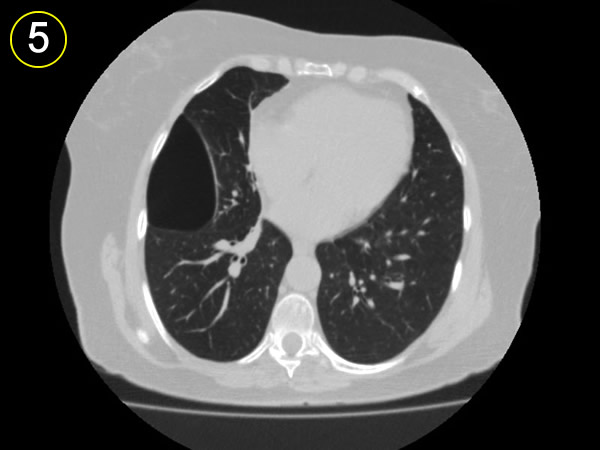

La tomografía

computarizada del tórax

y su adecuada interpretación es de gran ayuda diagnóstica

en las patologias del tórax.